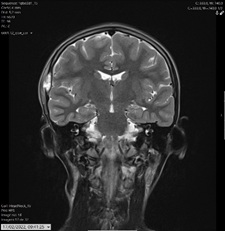

After two days, she had a magnetic resonance imaging (MRI) that confirmed the suspicion of Langerhans cell histiocytosis (LCH) (Figures 3 and 4).

Figure 3: Coronal T2-W MRI of the brain showing parietotemporal lesion, with adjacent soft tissue involvement.